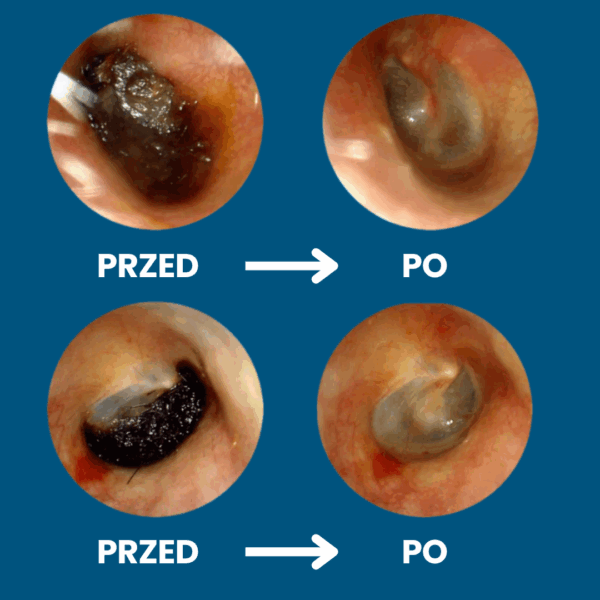

✅ Usuwa zalegającą woskowinę – nie wpycha jej głębiej jak tradycyjne patyczki

Koniec z ryzykiem urazów i infekcji — patyczki często powodują podrażnienia, infekcje i perforację błony bębenkowej. Pełna kontrola dzięki obrazowi HD 1080p — widzisz woskowinę i swobodnie ją usuwasz, zamiast ją wpychać.

Pełna kontrola dzięki obrazowi HD 1080p — widzisz woskowinę i swobodnie ją usuwasz, zamiast ją wpychać. Miękkie silikonowe końcówki zamiast patyczków — precyzyjnie usuwa woskowinę, bez ryzyka zarysowań i dyskomfortu

Higieniczne i oszczędne — wielorazowe końcówki redukują odpady i koszty wymiennych patyczków. Szybka ulga — natychmiastowy efekt komfortu i czystości uszu bez wizyt u specjalisty.

Szybka ulga — natychmiastowy efekt komfortu i czystości uszu bez wizyt u specjalisty.